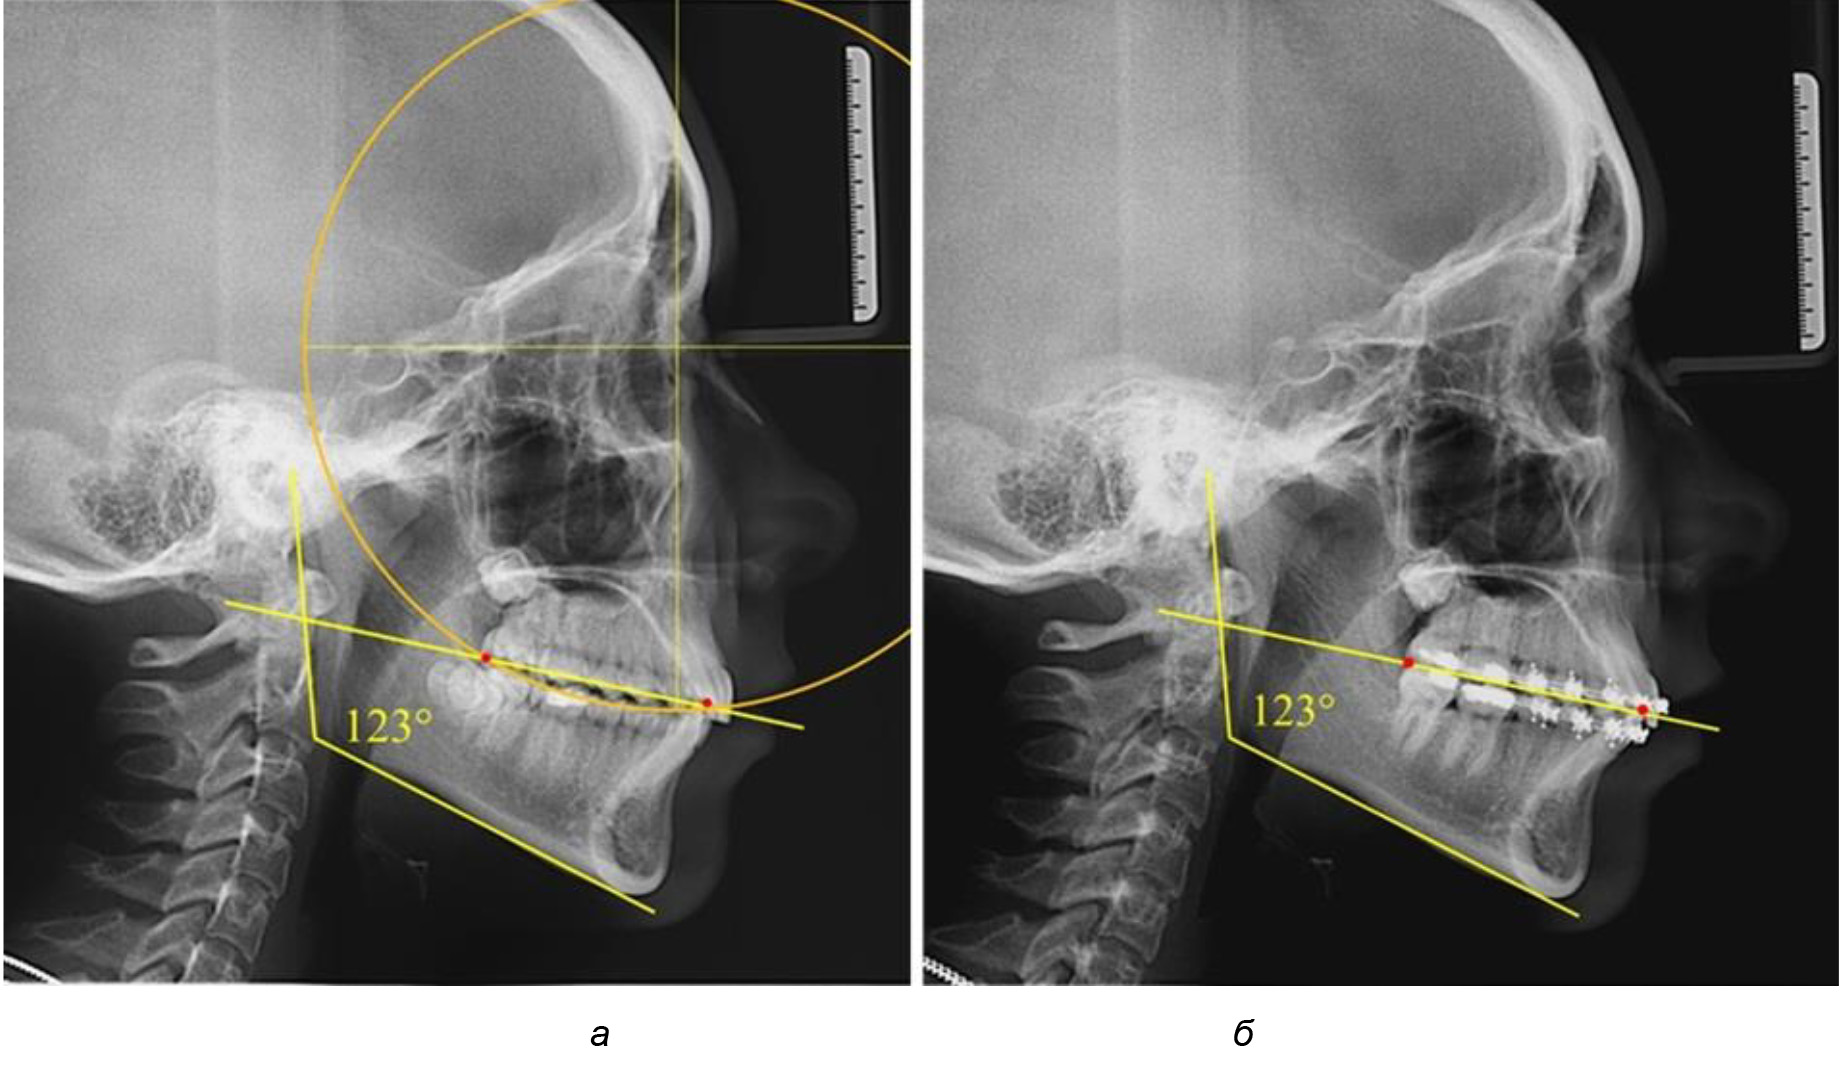

Таким образом, проведенное лечение техникой «прямой» дуги способствует нормализации окклюзионного равновесия и торку передних зубов, однако не соответствует оптимальному окклюзионному статусу, характеризующему физиологическую окклюзию. При этом величина нижнечелюстного угла оставалась на прежнем уровне (рис. 5).

Рис. 5. Особенности ТРГ при патологической кривой Spee до лечения (а) и после лечения (б) техникой «прямой» дуги

После лечения пациентов техникой «прямой» дуги, так же как и в 1-й подгруппе, было отмечено увеличение сагиттального размера окклюзионной лини в среднем на (2,38 ± 0,83) мм. Окклюзионная линия практически касалась окклюзионного контура всех жевательных зубов, и отмечалось практически полное отсутствие кривой Spee, так же как и у людей 1-й подгруппы 2-й группы (рис. 6).

Рис. 6. Особенности ТРГ при оптимальной кривой Spee до лечения (а) и после лечения (б) техникой «прямой» дуги

Таким образом, проведенное лечение техникой «прямой» дуги способствует нормализации окклюзионного равновесия и торку передних зубов, однако не соответствует оптимальному окклюзионному статусу, характеризующему физиологическую окклюзию. При этом величина нижнечелюстного угла оставалась на прежнем уровне.